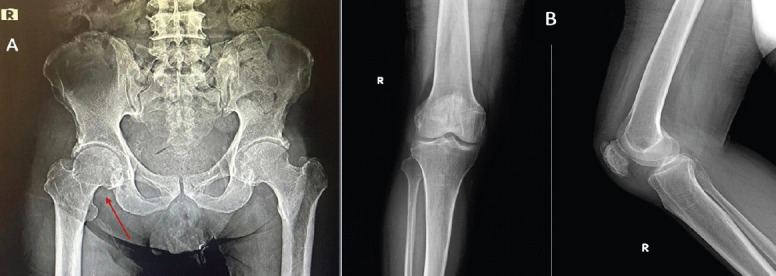

Case report: A 65-year-old male patient presented to the hospital with sudden inability to bear weight on his right lower limb, inability to flex the knee, which was associated with swelling of the knee, and the limb was externally rotated for 3 days. A fracture of the right neck of the femur was identified on X-ray of the pelvis with bilateral hips. There was no history of trauma. He is a known case of chronic kidney disease for 3 years and is also a known hypertensive and type 2 diabetes mellitus for 15 years, and is currently undergoing dialysis thrice per week. The affected knee was aspirated and was found to have S. marcescens infection, localized there itself; blood culture and intraoperative hip aspirate were negative for the same organism. He underwent right knee arthrotomy with synovectomy and was started on IV antibiotics based on the culture and sensitivity report.